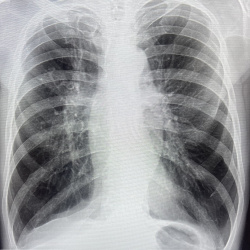

Пожилая женщина. Пришла на рг пкоп. Справа тень паразитарной кисты?